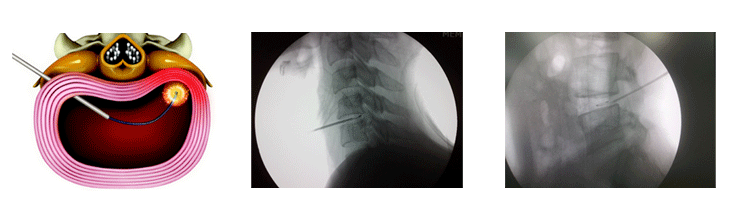

¸ñ µð½ºÅ© º´À̳ª Ç㸮 µð½ºÅ© º´¿¡¼ ¼¶À¯·ûÀÌ ÆÄ¿µÇÁö ¾ÊÀº °æ¿ì, º¸Á¸Àû Ä¡·á¿Í ½Å°æ ÁÖ»ç ¿ä¹ý¿¡µµ Áõ»óÀÌ Áö¼ÓµÇ´Â °æ¿ì, 0.8mm Â¥¸® ¹Ì¼¼ÁÖ»ç¹Ù´ÃÀ» ÅëÁõ ¿øÀÎ µð½ºÅ© ¾ÈÀ¸·Î »ðÀÔÇÑ ÈÄ Ã´Ã߽ŰæÀ» ¾Ð¹ÚÇÏ´Â µð½ºÅ© ¼öÇÙ°ú ¼¶À¯·ûÀ» Àú¿Â °íÁÖÆÄ(Çö󽺸¶ Àå)·Î µð½ºÅ© ³»ÀÇ ¼öÇÙÀÇ Á¶Á÷À» ºü¸£°Ô ºÐÇØÇÏ°í ³ì¿©¼ Á¦°ÅÇÏ°í ³ª¿À¸é¼ ¼öÇÙÀ» ¼öÃà ÀÀ°íÇÏ¿© µð½ºÅ©°¡ ÇØ´ç ½Å°æÀ» ¾Ð¹ÚÇÏ´Â °ÍÀ» °¨¾ÐÇÔÀ¸·Î½á Ä¡·áÇÏ´Â ¹æ¹ýÀÔ´Ï´Ù.

±¹¼Ò¸¶Ãë ÈÄ ²¿¸®»À ºÎÀ§¸¦ ÅëÇÏ¿© Ư¼öÇÏ°Ô Á¦ÀÛµÈ Áö¸§ 1~2§® Ä«Å×Å͸¦ Á÷Á¢ Á¶ÀÛÇÏ¿© ½Å°æ¸· ÁÖÀ§ À¯ÂøÀ» ¹Ú¸®Çϰí ÇÊ¿äÇÑ ºÎÀ§¿¡ Àç À¯ÂøÀÌ ¹ß»ýÇÏÁö ¾Êµµ·Ï °íÀå¾× »ý¸® ½Ä¿°¼ö°ú È¥Çվ๰À» ÁÖÀÔÇÏ¿©, ÇØ´ç µð½ºÅ©ÀÇ ¾à°£ÀÇ ÀÀÃà, ½Å°æÀÇ ¿°Áõ°ú ºÎÁ¾ °¨¼Ò, ½Å°æ ÁÖº¯ÀÇ ¹Ì¼¼ ÈäÅÍÁ¶Á÷/¼¶À¯È Á¶Á÷À» ¹Ú¸®ÇÏ¿© Ä¡·áÈ¿°ú¸¦ ³»´Â ½Ã¼ú·Î¼ Áߵ ÀÌÇÏÀÇ µð½ºÅ© º´À̳ª ôÃß ÇùÂøÁõÀ» Ä¡·áÇÒ ¼ö ÀÖ½À´Ï´Ù. ÃÖ±Ù¿¡´Â ¹Ú¸®È¿°ú¿Í ¾à¹° Àü´Þ °ø°£ È®º¸¸¦ Áõ°¡½Ã۱â À§ÇØ Ç³¼± ½Å°æ¼ºÇü¼úÀ» ½Ã¼úÇϱ⵵ ÇÕ´Ï´Ù.